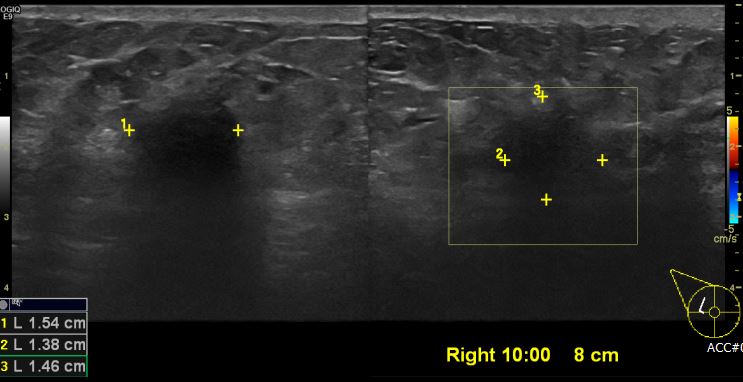

상기환자 우측 유방 비대층과, 통증있어 내원하신 50대 여성분으로 우측 10시 방향 에서 8cm 떨어진 거리의 의심스러운 혹 조직검사 시행하여 우측 침윤성 유관암 진단 되었습니다.